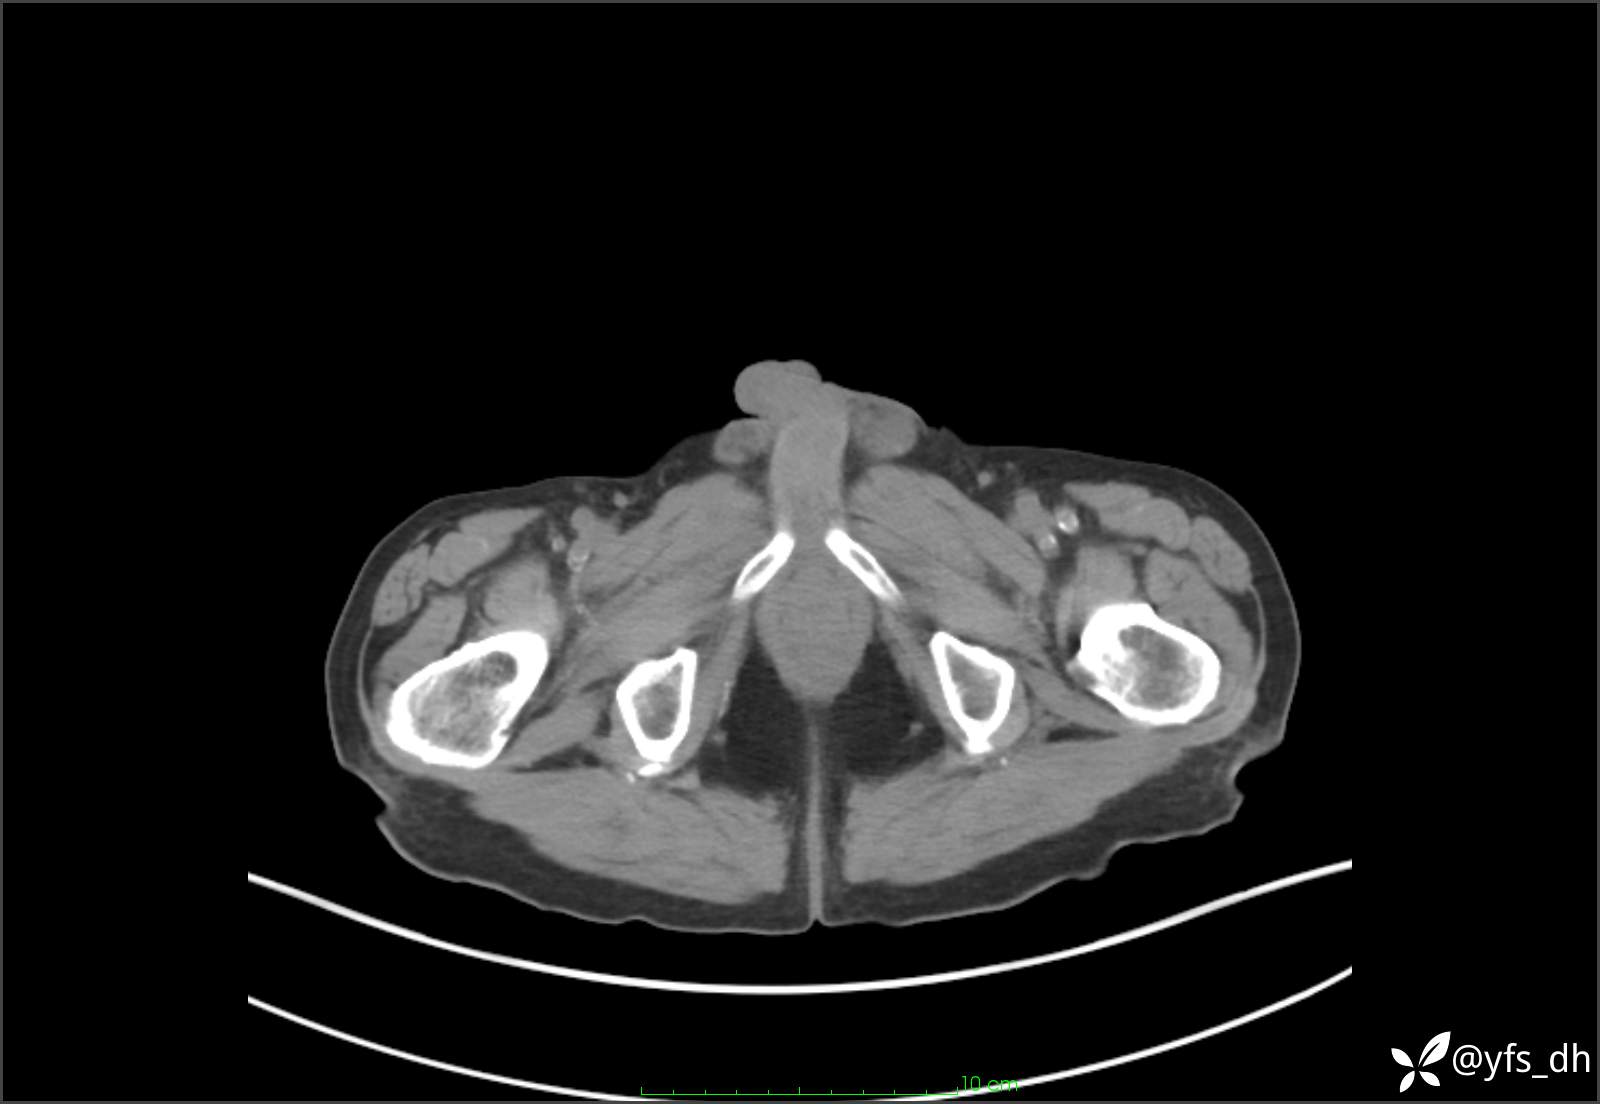

1.简要病史:患者4天前突发上腹部疼痛不适,但可以忍受。3小时前饭后突然加重,不能忍受后就诊。

2.简要手术记录:术中见腹盆腔大量肠液及粪便,乙状结肠中下段见一约3cm的破口。